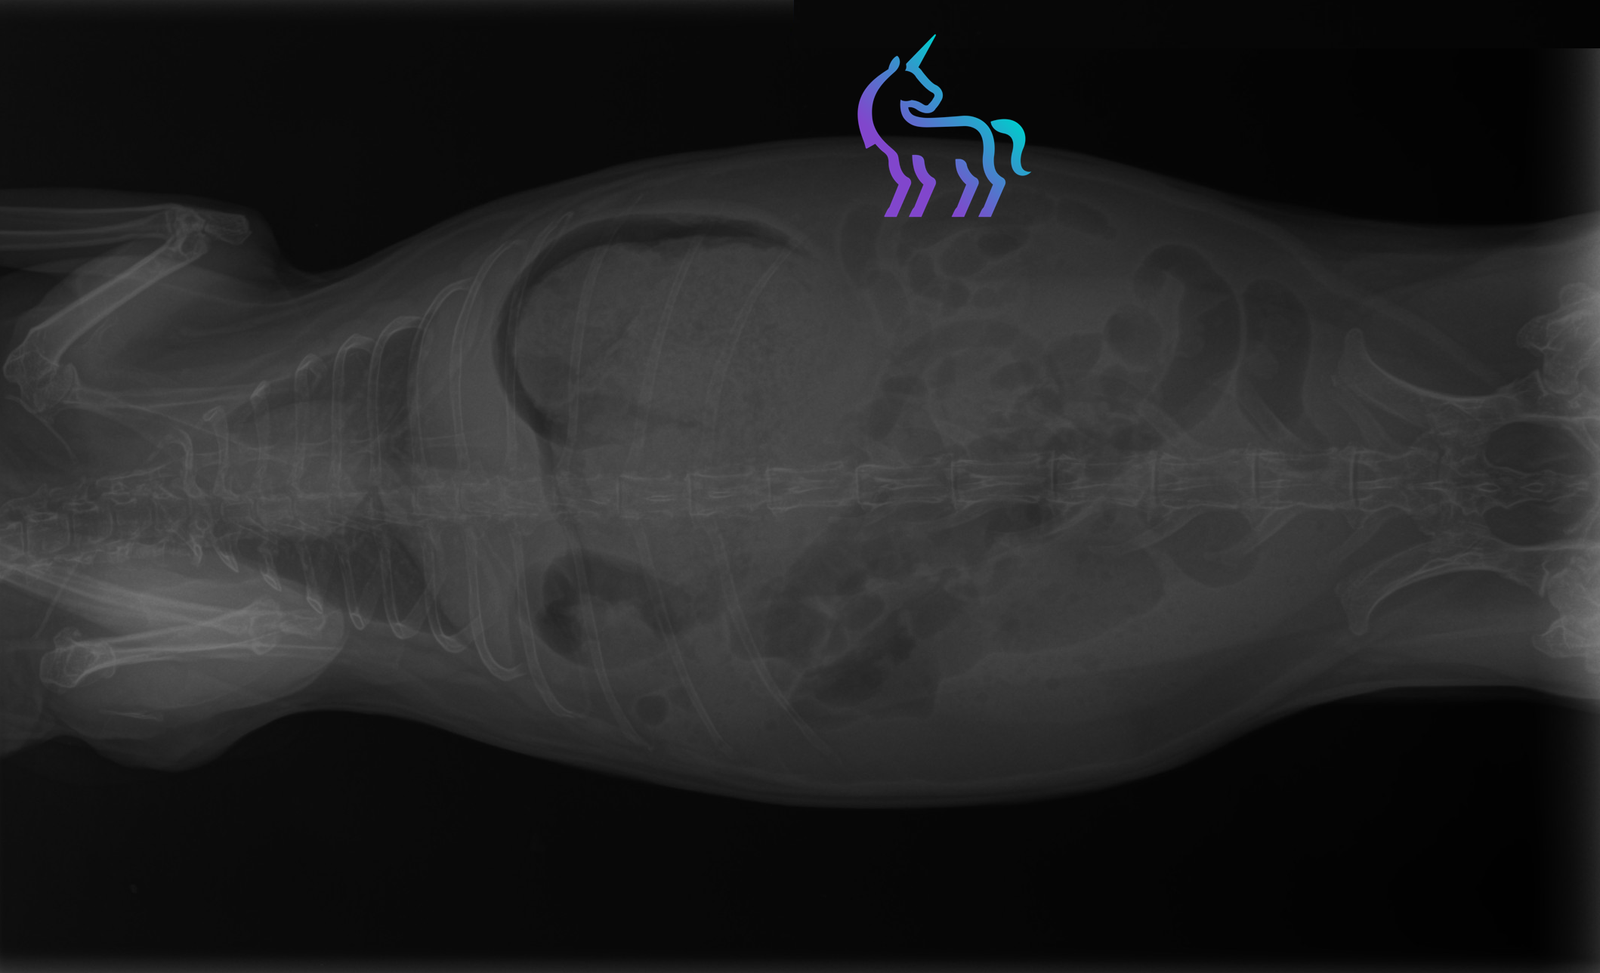

Quels examens sont utiles ?

Radiographies pour fractures/arthrose, scanner/IRM si suspicion lésion vertébrale.Amputation : dans quels cas ?

Radiographies (poumons), prélèvements bactériologiques ou scanner.7) Oreilles (otites) et chirurgie de l’oreille

Radiographie, échographie et analyse sanguine.Cystotomie : c’est quoi et quand ?